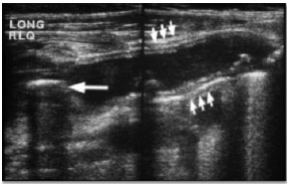

“Paciente, jovem, com queixa de dor abdominal, de início há 2 dias, com localização inespecífica, e agora bem localizada em fossa ilíaca direita, é submetido à ultrassonografia da região, a qual é esclarecedora e apresenta os seguintes achados de imagem.”

Com base no disposto, é correto afirmar que trata-se, provavelmente, de